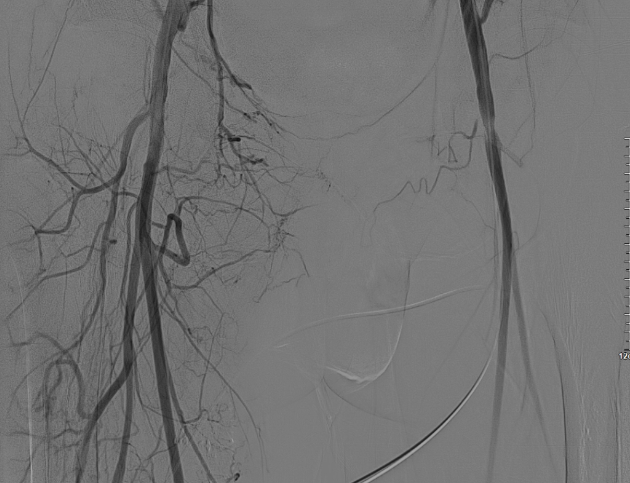

髂动脉重建

该图解释为何远端距离双侧髂总动脉分叉至少1.5cm,以避免后扩张时大球囊对髂动脉造成损伤。

CERAB技术的关键点一:经双侧股总动脉植入2枚VBX球囊扩张式覆膜支架(8L×79mm),与腹主动脉覆膜支架腔内平行放置,且两枚支架端平齐对接。

CERAB技术关键点二:先用14mm×40mm球囊分别扩张双侧髂肢的腹主动脉段。

再用8mm球囊对双侧髂支腹主动脉段行对吻扩张,以确保双侧髂支与腹主动脉覆膜支架腔内获得良好的贴壁形态,最大程度减少空腔,降低远期再狭窄发生率。